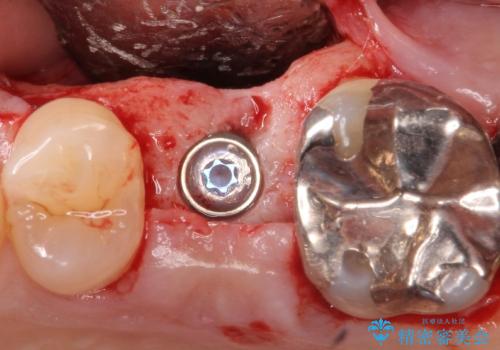

歯茎が腫れる インプラントでの治療

- 40代女性

- 10ヶ月

- 5-10回

- 左上5/インプラント:242,000円 骨増生:55,000円 カスタムアバットメント:110,000円 インプラント用仮歯:22,000円 ジルコニアクラウン:121,000円 合計550,000円費用は治療当時の料金となります